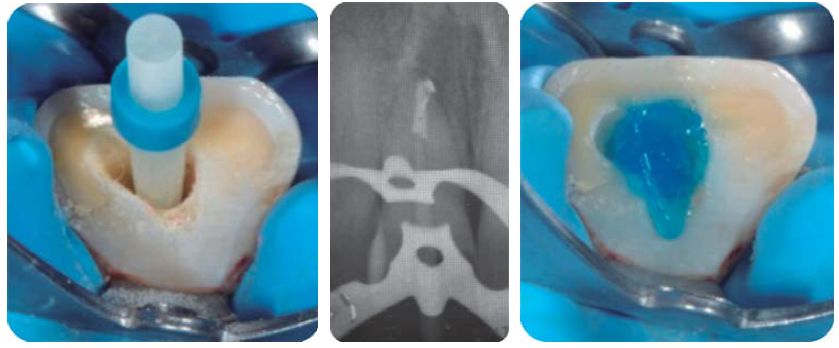

Reconstrucción con postes de fibra de vidrio

Con aislamiento absoluto, se realiza la desobturación con instrumentos de compactación vertical de Schilder, se toman radiografías control de desobturación y ajuste de los postes de fibra de vidrio RelyXTM Fiber Post® 1.3Ø amarillo (3M ESPE). Se graba con ácido fosfórico al 37% por 20 seg, se lava el conducto con espray de agua y se seca con puntas de papel; el cementado del endoposte de fibra de vidrio y la reconstrucción coronal se realiza con el sistema del cemento resinoso Rebilda DC® (VOCO) (Figura 12), se toma radiografía control de la cementación.19,20 Cuidando exhaustivamente el protocolo de adhesión, una vez reconstruidos y preparados, se planifica cementar con ionómero de vidrio los provisionales de larga duración de Telio Lab (Ivoclar Vivadent), para mayor comodidad y estética del paciente (Figura 13).21

Reconstrucción con poste de fibra de vidrio

Con aislamiento absoluto, se realiza la desobturación usando instrumentos de compactación vertical de Schilder ®, se toman radiografías de control de desobturación y ajuste del poste de fibra de vidrio RelyX Post ® 1.9Ø de la casa comercial 3MTM ESPE. Para continuar con el grabado, lavado, secado del conducto (Figura 20), cementado del endoposte de fibra de vidrio y finalizando con la reconstrucción coronal con el sistema del cemento resinoso Rebilda ® DC (VOCO) y radiografía control de cementación (Figura 21).19,20

Desobturación con instrumentos de compactación vertical de Schilder, tratando de sellar mejor al momento de termoplastificar la gutapercha, se toma radiografía control de desobturación, observando que el Drill del sistema a utilizar queda con espacios (Figura 29 A), se ajuste del poste de fibra de vidrio FRC Postec ® Plus tamaño 3, de la casa comercial Ivoclar Vivadent, cuyo diámetro coronal es de 2 mm y el apical de 1 mm (Figura 29 B). Se corta el poste de fibra de vidrio en una intensión con pieza de alta velocidad, fresa de diamante grano grueso y abundante irrigación, luego se graba, se lava, se seca el conducto y se cementa el endoposte de fibra de vidrio con la parte coronal del mismo hacia apical del conducto para de esta forma ser más congruentes con el diámetro de un diente joven y el excedente apical del poste se introduce como poste complementario en coronal del conducto, la cementación y reconstrucción coronal se realizó con el sistema del cemento resinoso Rebilda DC ® (VOCO), finalmente se toma una radiografía control de cementación (Figura 29 C).

Figura 29 A) Desobturación. B) Prueba del poste de fibra de vidrio. C) Cementación del poste de fibra de vidrio.

Siendo extremadamente conservadores y con el objetivo de restaurar con corona de cerómero (SR Adoro, Ivoclar Vivadent), se toma la impresión con polivinilsiloxano de 3M (Express ®) usando la técnica de separación gingival a doble hilo (Figura 30).

Figura 30 Separación gingival a doble hilo para toma de impresión, oclusal de la cementación del poste de fibra de vidrio y colocación de hilos.